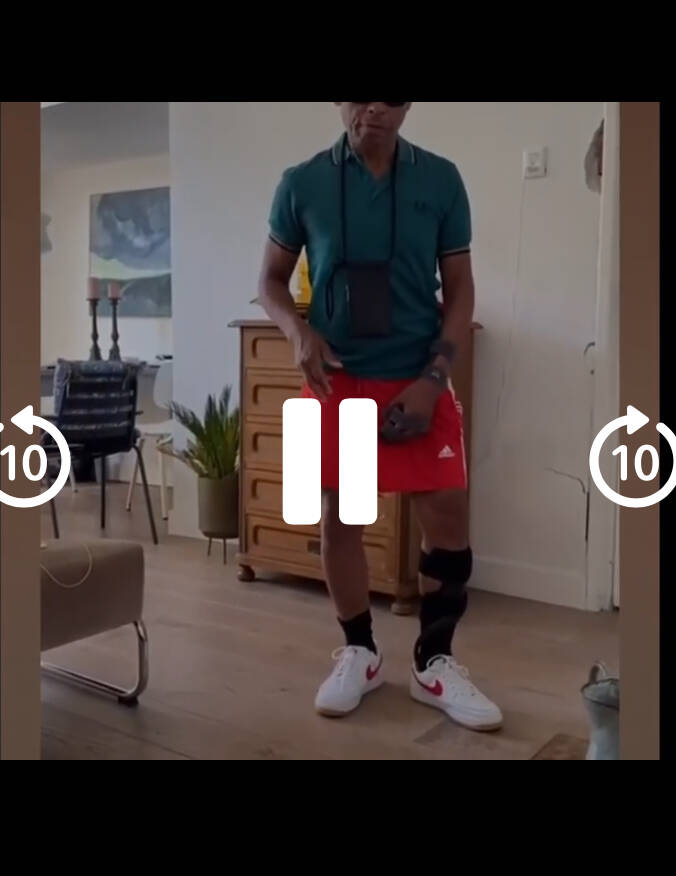

5,. I ga momenteel twee keer per week voor onderhoud naar fysiotherapiepraktijk Leidsevaart in Haarlem wat ongeveer 600 meter van mijn huis verwijderd is.

De resultaten na hard revalideren

Eerste keer dat ik thuis los loop zonder hulpmiddelen

Na mijn herseninfarct heb ik staand badminton en het zwemmen herontdekt. Ook fiets ik weer regelmatig. Deze sporten geven mij energie en helpen mij om fit te blijven. Het is geweldig om te ervaren dat ik nog steeds actief kan zijn en plezier kan hebben in sport, ondanks mijn beperkingen.